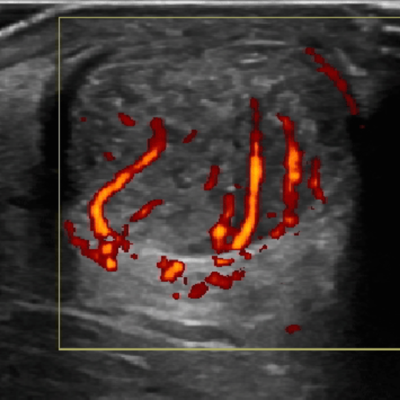

Foot and Ankle Pain Diagnosis with Point-of-Care Ultrasound

Master the use of point-of-care ultrasound to diagnose foot and ankle pain. This webinar blends anatomy-driven insights with ultrasound techniques to evaluate musculoskeletal and neuropathic conditions. Learn practical approaches for identifying both...